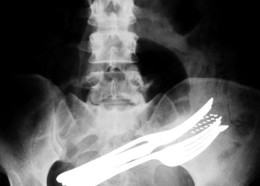

Чудни ренгенски снимки

Фото на денот #630